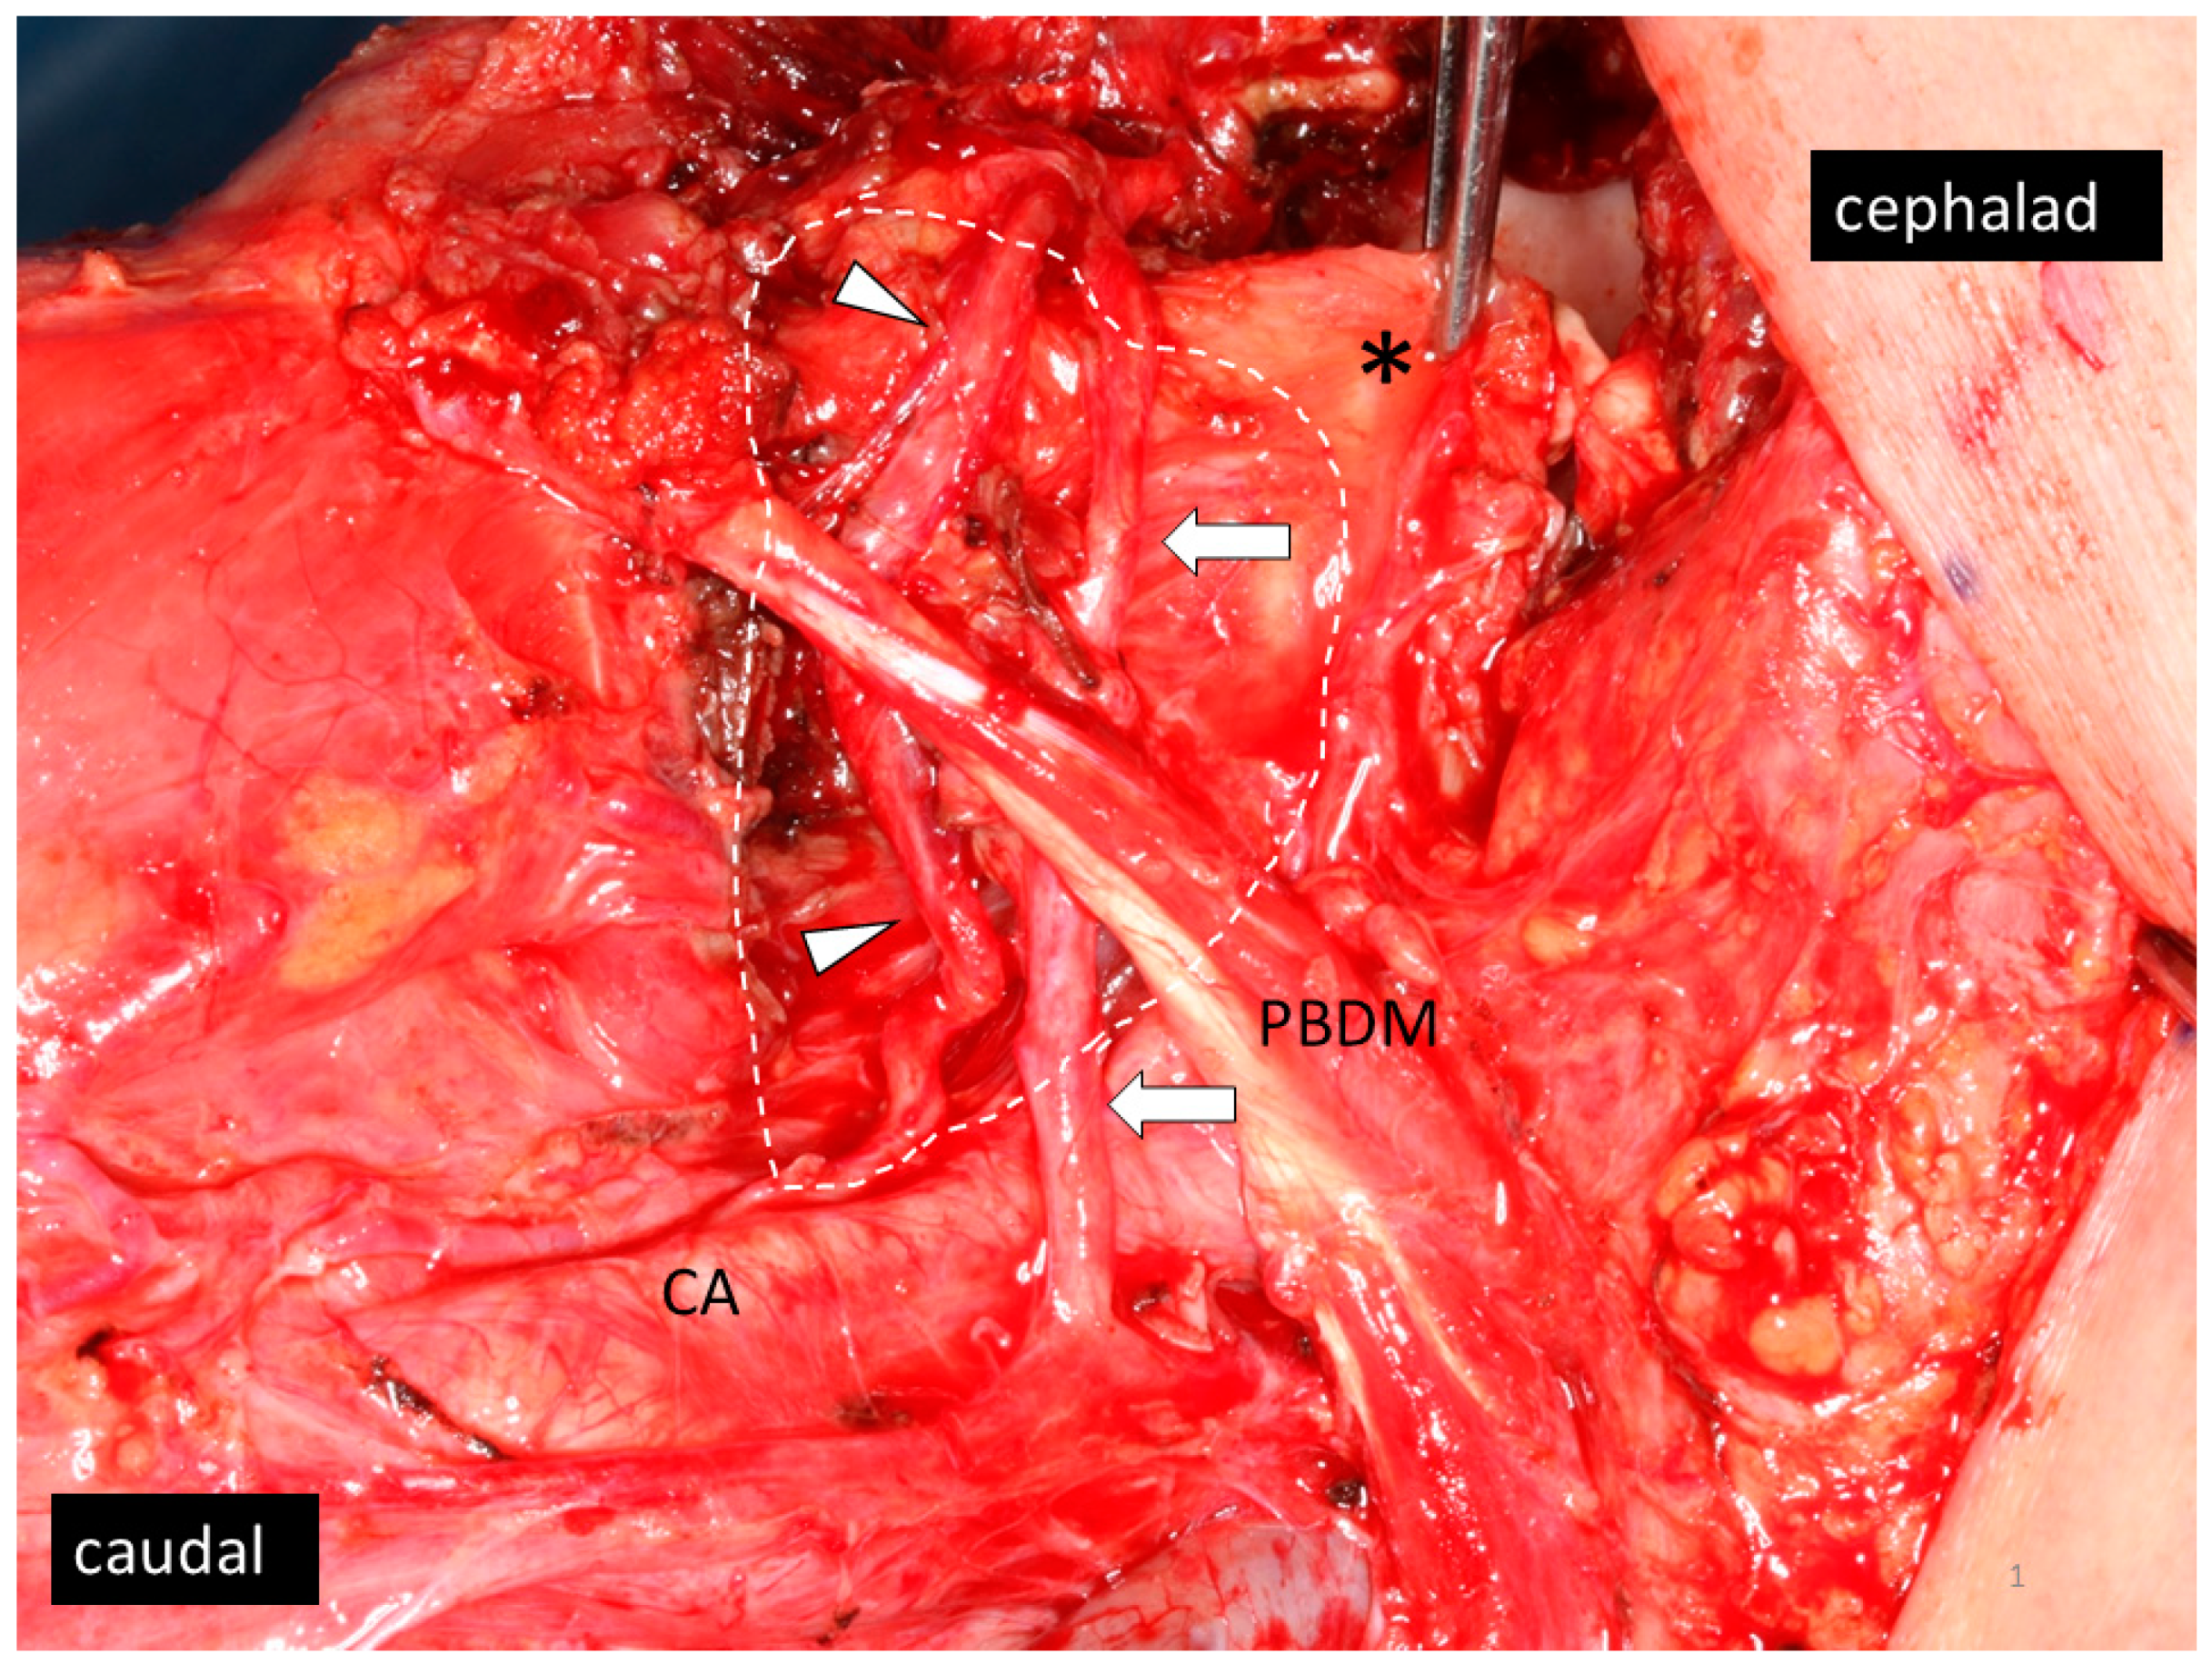

- Ando, M.; Asai, M.; Ono, T.; Nakanishi, Y.; Asakage, T.; Yamasoba, T. Metastases to the lingual nodes in tongue cancer: A pitfall in a conventional neck dissection. Auris Nasus Larynx 2010, 37, 386–389. [Google Scholar] [CrossRef] [PubMed]

- Umeda, M.; Minamikawa, T.; Shigeta, T.; Oguni, A.; Kataoka, T.; Takahashi, H.; Shibuya, Y.; Komori, T. Metastasis to the lingual lymph node in patients with squamous cell carcinoma of the floor of the mouth: A report of two cases. Kobe J. Med. Sci. 2010, 55, E67–E72. [Google Scholar] [PubMed]